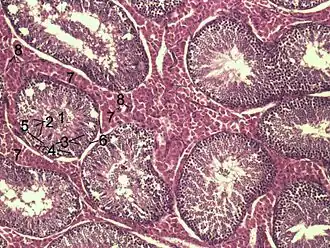

![]() Histological section through testicular parenchyma of a boar. 1 Lumen of tubulus seminiferus contortus, 2 spermatids, 3 spermatocytes, 4 spermatogonia, 5 Sertoli cell, 6 Myofibroblasts, 7 Leydig cells, 8 capillaries | |